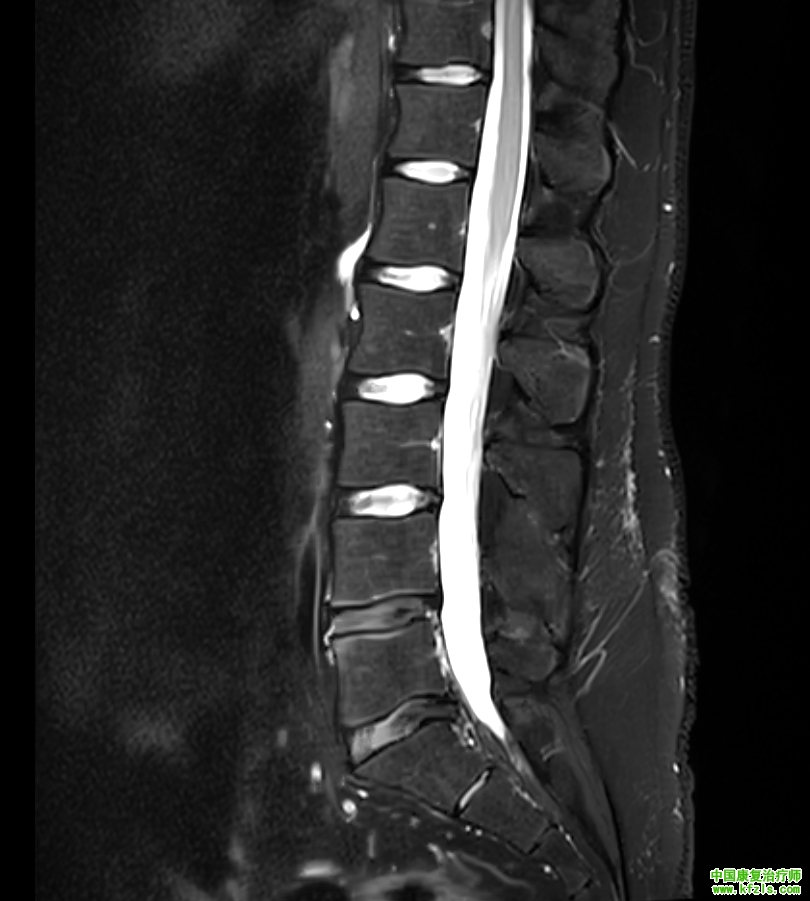

一位34岁绘画老师,男性,主诉是腰部疼痛,伴随右侧放射性麻木到大腿,长时间坐着酸胀感增加,无法搬重物,弯腰疼痛。医院拍片发现双侧椎间孔狭窄,L4/L5,L5/S1椎间盘突出,卡压神经根。直腿抬高试验阳性,slump试验阳性,弯腰测试阳性。

f4940fd6cb609653082a80c604d593b3.png

a00343da74c7834a7b73f62d4cb96ae3.png

3fbf834e35c48b70b4481a499a228fa5.png

*根据以上症状,我们给出了具体康复治疗方案